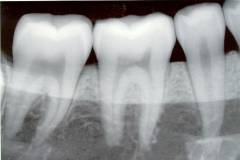

Диагностика кариеса

Диагностика кариеса должна осуществляться на самых ранних стадиях. Чем раньше выявлен патологический процесс, тем проще и эффективнее будет его лечение.

Во время планового посещения врач проводит осмотр зубов, при необходимости назначает дополнительное обследование (рентгенография), дает рекомендации по уходу за ротовой полостью. При необходимости по желанию пациента выполняется профессиональная чистка зубов, герметизация ямок и щелей на их поверхности, обработка растворами фтора.